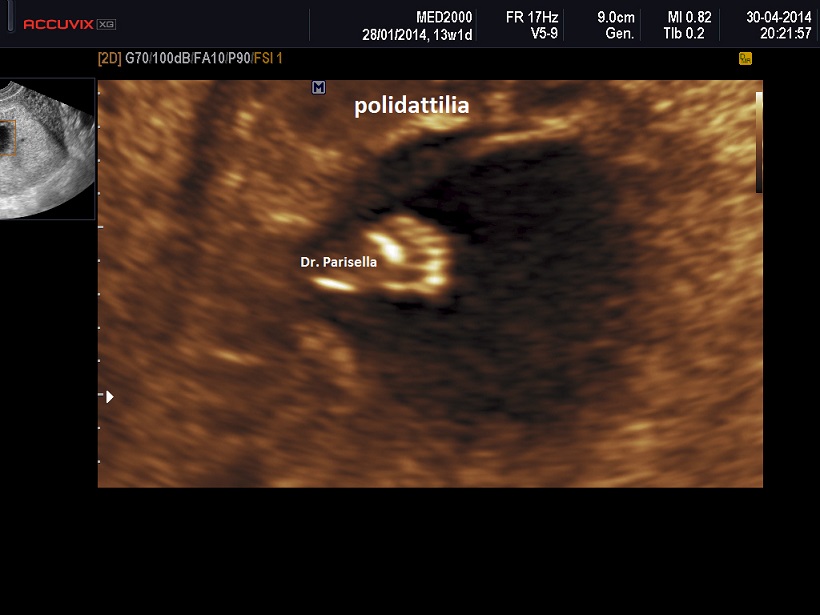

Le lesioni caratteristiche a carico del SNC sono rappresentate  da idrocefalo grave, con ventricoli aperti nello spazio subaracnoideo, ipoplasia cerebrale, anomalie della linea mediana e del setto pellucido (agenesia del corpo calloso); possono essere presenti encefalocele occipitale, una caratteristica conformazione del forame magno “key-hole shaped”, mandibola piccola e naso malformato, labio-palatoschisi. Caratteristica è la polidattilia postassiale alle mani e preassiale ai piedi (l'alluce duplice è altamente caratteristico, quasi esclusivo, di questa condizione morbosa). Segnalati anche piede torto e difetti cardiovascolari (difetti del setto atriale; atrio unico). Come ha segnalato lo studio di Salonen e coll. (1981) condotto su 28 neonati di 18 famiglie, l'esito abituale della gravidanza è la nascita di feto morto o morte in epoca neonatale.

La Diagnosi Prenatale si basa su: 1) assenza di movimenti attivi fetali; 2) polidattilia postassiale alle mani; 3) polidattilia preassiale ai piedi;  4) idrocefalia; 5) polidramnios.